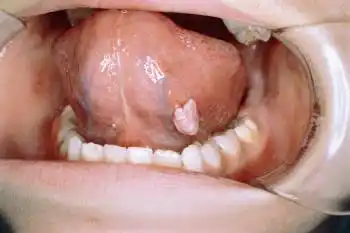

口腔感染hpv舌头图片

可见菜花状新生物从以上图片可以看出:口腔尖锐湿疣皮疹隆起呈乳头状